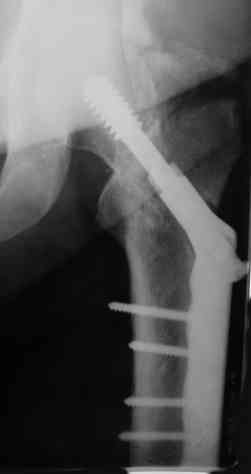

Вальгизирующая остеотомия по Marti с латерализацией, фиксация клинковой

пластиной (см. рис.) - хотя результат менее предсказуем, чем при эндпротезировании.

Поэтому отбрасывая все остальное, считаем, что Intertrochanteric valgus osteotomy или Межвертельная вальгусная остеотомия создает те необходимые биомеханические преимущества, которые восстановят измененную биомеханику.

Среди всех остальных этот вариант является менее инвазивным, отличный результат от 75-90%, отсутствует дополнительный риск повреждения кровоснабжения головки бедра, и главное - биомеханические преимущества.

Технически все делается внесуставно, без вскрытия места ложного сустава, в положение больного на спине, для облегчения работы ближе к краю операционного стола.

На вертеле делается "срез" в латеральном кортекса для клинка пластины и специальное долото вводится под 90-градусным углом к бедру по заранее приготовленному предоперационному плану.

Делается межвертельная остеотомия с удалением клина в 20-30 градусов в зависимости от шеечно-диафизарного угла, а все остальное сделает 120 градусная Blade Plate.

Для предупреждения вальгуса механической оси конечности необходима латеризация бедра, кусок кости от остеотомии, уложеный между пластиной и латеральным кортексом, латерализует бедренный диафиз.

На представленных снимках некоторые моменты, предоперационный план, латерализация, расчет длины, ориентир для введения и наборы.